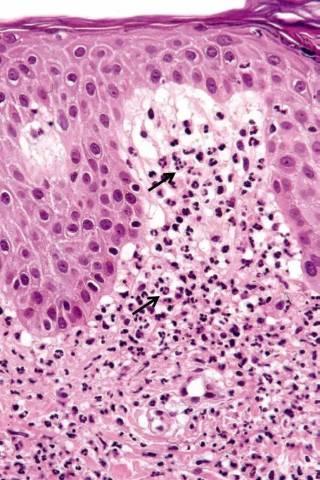

中性粒细胞是在瑞氏(Wright)染色血涂片中,胞质呈无色或极浅的淡红色,有许多弥散分布的细小的(0.2~0.4微米)浅红或浅紫色的特有颗粒。细胞核呈杆状或2~5分叶状,叶与叶间有细丝相连。

中性粒细胞来源于骨髓,具有分叶形或杆状的核,胞浆内含有大量既不嗜碱也不嗜酸的中性细颗粒,中性粒细胞具趋化作用、吞噬作用和杀菌作用。

这些颗粒多是溶酶体,内含髓过氧化酶、溶菌酶、碱性磷酸酶和酸性水解酶等丰富的酶类,与细胞的吞噬和消化功能有关。